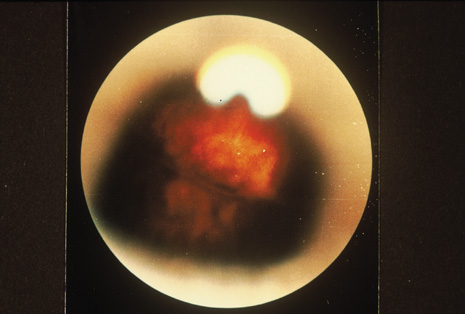

Although keratocentesis had been advocated historically as a treatment for active uveitis, it lost the attention of ophthalmologists until 1919, when Bruckner3 first examined the aqueous humor for diagnostic purposes. Laboratory techniques were revolutionized in the 20th century in areas such as: (a) evaluating very small aliquots of fluid (0.2 to 0.3 mL of aqueous or vitreous), and (b) identifying specific microbial organisms and the predominance of other cell types, antibodies, and proteins in these fluids (Figs. 1, 2, 3, 4, 5, and 6). These advancements have led to the development of diagnostic paracentesis for sight-threatening ocular inflammations that are difficult to diagnose. Witmer4 and O'Connor5 have provided strong evidence that samples of the aqueous humor reflect the antibody-producing capabilities of the iris and ciliary body, particularly when more specific antibody per unit of gamma globulin can be found on the aqueous humor than in the blood of the same patient.6–8 These determinations may be highly significant when one considers the fact that diseased tissue is being bathed in an antibody-containing fluid that is elaborated locally. For instance, in the case shown in Figure 1, the immunofluorescent antibody titer to toxoplasmosis is four times greater in the vitreous aspirate at the time of vitrectomy for repair of retinal detachment than in the plasma. These same considerations have long been recognized in syphilis of the central nervous system, wherein specific antibodies may be present in the cerebrospinal fluid but not in the blood. This is also the case with an unusual presentation of ocular coccidioidomycosis9 or toxocariasis.

Precise identification and culture of bacterial and fungal pathogens from both the aqueous humor and the vitreous fluid can be obtained. Gram's stain and Giemsa's stain smears of centrifuged specimens from the aqueous humor and the vitreous humor frequently demonstrate the bacterial or fungal causative agent. Attempts to isolate bacteria and fungi and to identify them on Gram's stain or Giemsa's stain smears have been most rewarding in the following cases: (a) postoperative endophthalmitis, (b) infection after a penetrating injury of the eye, (c) drug abuse patients with endogenous endophthalmitis (Figs. 21, 22, 23, 24, and 25), (d) patients receiving hyperalimentation, and (4) patients who are immunocompromised as a result of exogenous immunosuppressive agents.